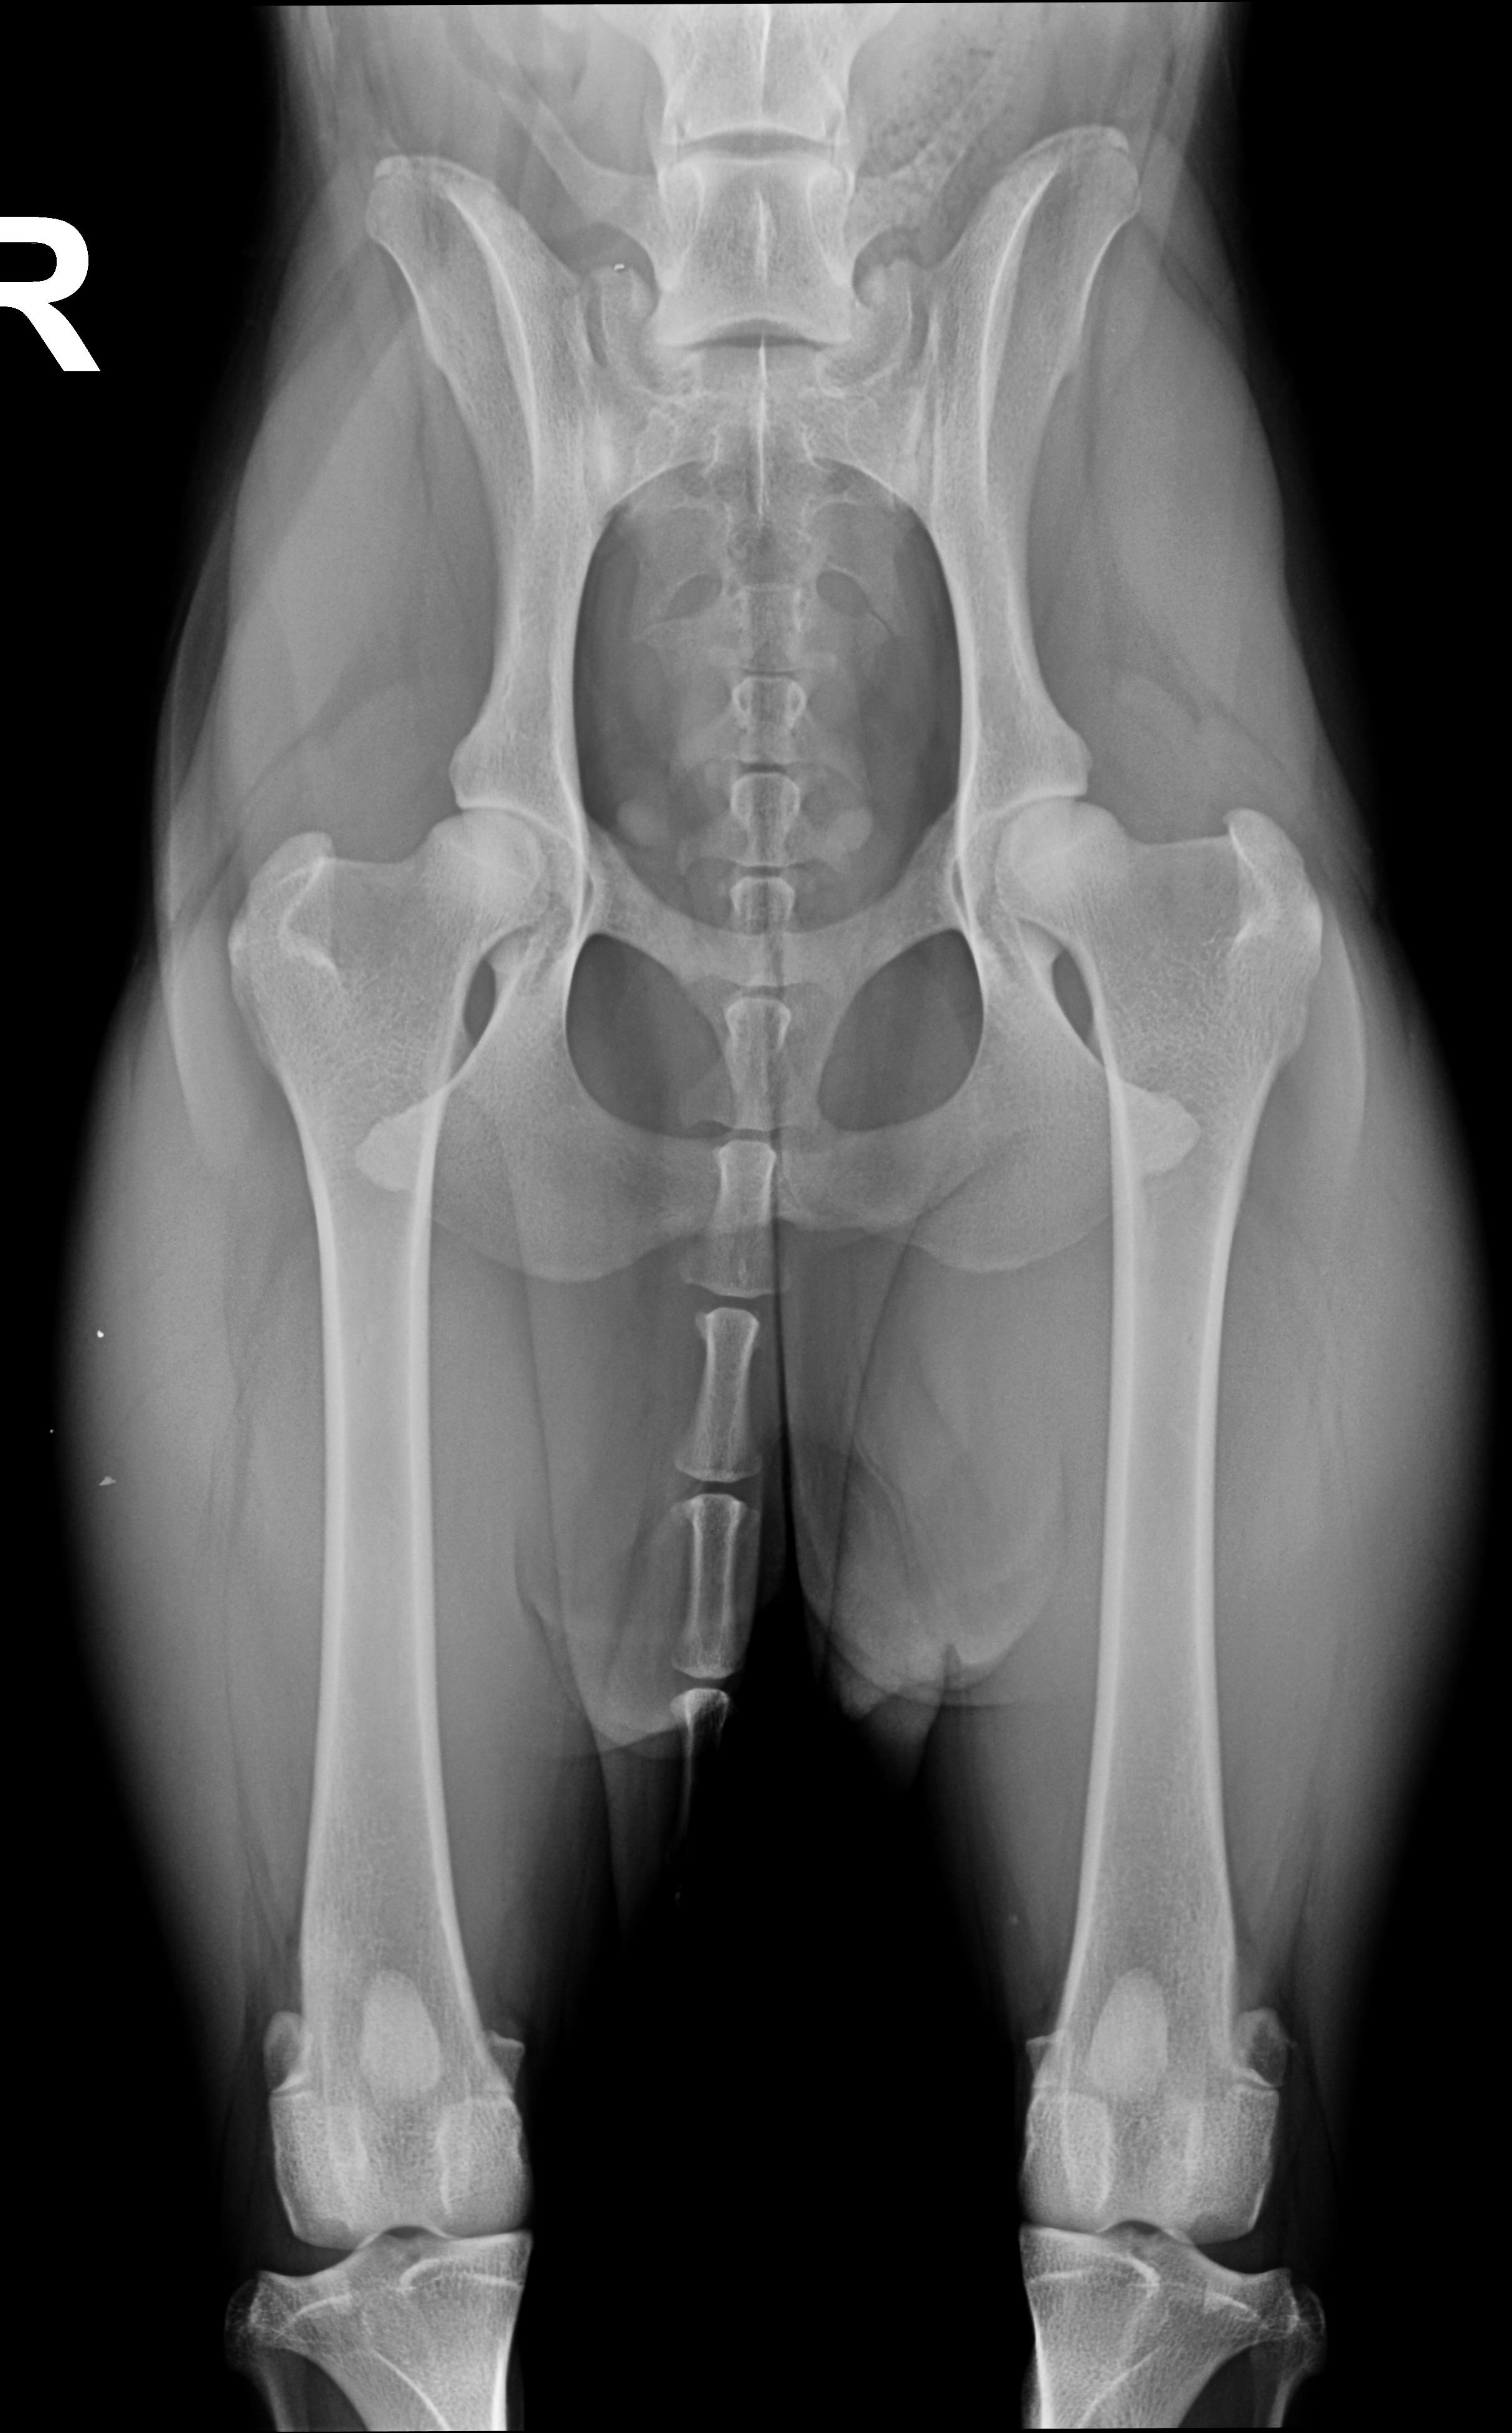

HD A2*, ED0, OCD frei, LÜW 0, Spondylose frei, Herzultraschall 14 Monate frei

* Dr Lämmer wertete T Rex HD B1 aus, darauf hin liess ich ein weiteres Gutachten bei Obergutachter Dr. Tellhelm anfertigen, der T Rex mit HD A2 auswertete. Dieses Ergebnis wird allerdings nur offiziell übernommen wenn ich meinen Hund erneut nach 6 Monaten Sperre in Narkose röntgen lasse und dieses Ergebnis noch einmal bestätigt wird. Bei aller Liebe diesem unnötigen Risiko setze ich meinen Hund NICHT aus. Ich habe keine Geheimnisse, deshalb lasse ich ihr Röntgenbild hier für alle transparent hoch: